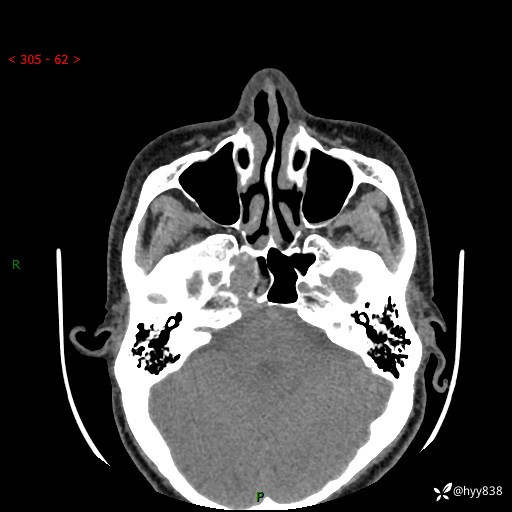

蝶鞍CT平扫